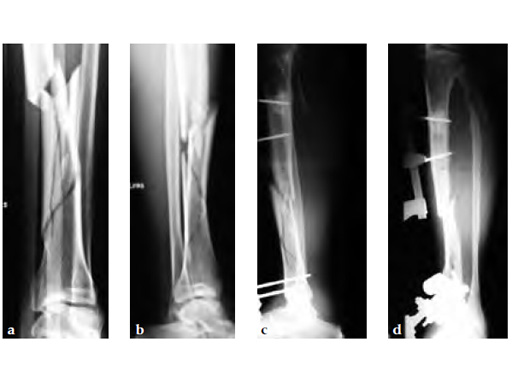

A 58-year-old male sustained a closed multifragmentary 42-C1 fracture in the distal tibia with compartment syndrome.

Case provided by Dankward Hntzsch, Tbingen, Germany

Primary treatment consisted of an external fixator and release of compartments.

Mobilization of the limb started with an applied external fixator.

Secondary treatment: insertion of an unreamed intramedullary nail with three ASLS screws inserted distally providing angular stability.